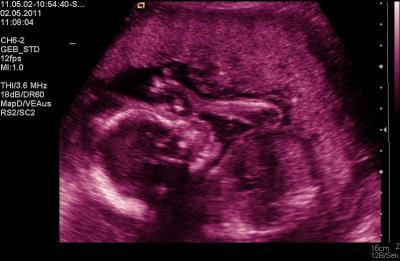

guten morgen alle zusammen, wir waren ja auch gestern zur fd in dresden. kurz bevor wir dran kamen war ich doch deutlich nervös, dass baby hats mir mit boxen gedankt. es war ein ganz lieber arzt, der uns alles super erklärte und auch immer meinte, wenn wir fragen haben, dann sollten wir fragen. die untersuchung ging ca. ne halbe stunde. am anfang boxte das baby doch paar male (aber von außen spürt man das noch nicht wirklich), aber es war eindeutig, ich merkte es und man sah es auch im ultraschall das die hand hoch ging... also linkerseits werde ich geboxt und rechterseits getreten ^^ das baby hatte ständig die linke hand vorm gesicht, also rüttelte der arzt einmal (was mir in dem moment nicht gerade "gut tat" aber es hat geholfen). es ist alles gut entwickelt und es gibt keine auffälligkeiten. die versorgung ist auch optimal, außerdem hat er uns alle finger und zehen zeigen können. das baby ist nun ca. 23 cm groß und hat ein gewicht von ca. 330 g, also passt es gut in die 21. woche (gestern war ich bei 20+5). zum schluss fragte ich noch, ob man sehen könnte was es denn nun ist. also schallte er nochmals kurz und fragte mich, wie mein bauchgefühl wäre. ich meinte, mädchen. dann fragte er, was mein arzt dazu meinte. da meinte mein verlobter, dass er das nicht richtig sehen konnte, da beim letzten ultraschall die nabelschnur schön davor lag. also zeigte er uns was es nun ist und ich hatte recht. wir bekommen ein kleines mädchen. soo... zur "shopping-tour"... ich wollte doch unbedingt eine spieluhr für´s baby kaufen... aber neeee... mit was sind wir heimgekommen???? mit babymöbeln , d.h. wir haben jetzt ein bett (umbaubar zum juniorbett), einen kleiderschrank und eine wickelkomode, für alles zusammen 415 euro. es fehlt dann lediglich noch einlagefächer für den schrank (lassen wir im baumarkt machen... ist viel billiger), dann ne wickelkomodenauflage und fürs bett ne matratze, bettlaken (waren mir im möbelladen zu teuer). so, die ganzen kartons sind jetzt im kinderzimmer und nächsten monat wollen wir mit dem aufbau anfangen, damit es ordentlich "gelüftet" werden kann... stinkt ja immer sooo lange. so... ich füge mal noch 1 bildchen mit ein, das am schönsten ist ;)

Bild zu bericht von gestern (fd) - Forum für September - Mamis